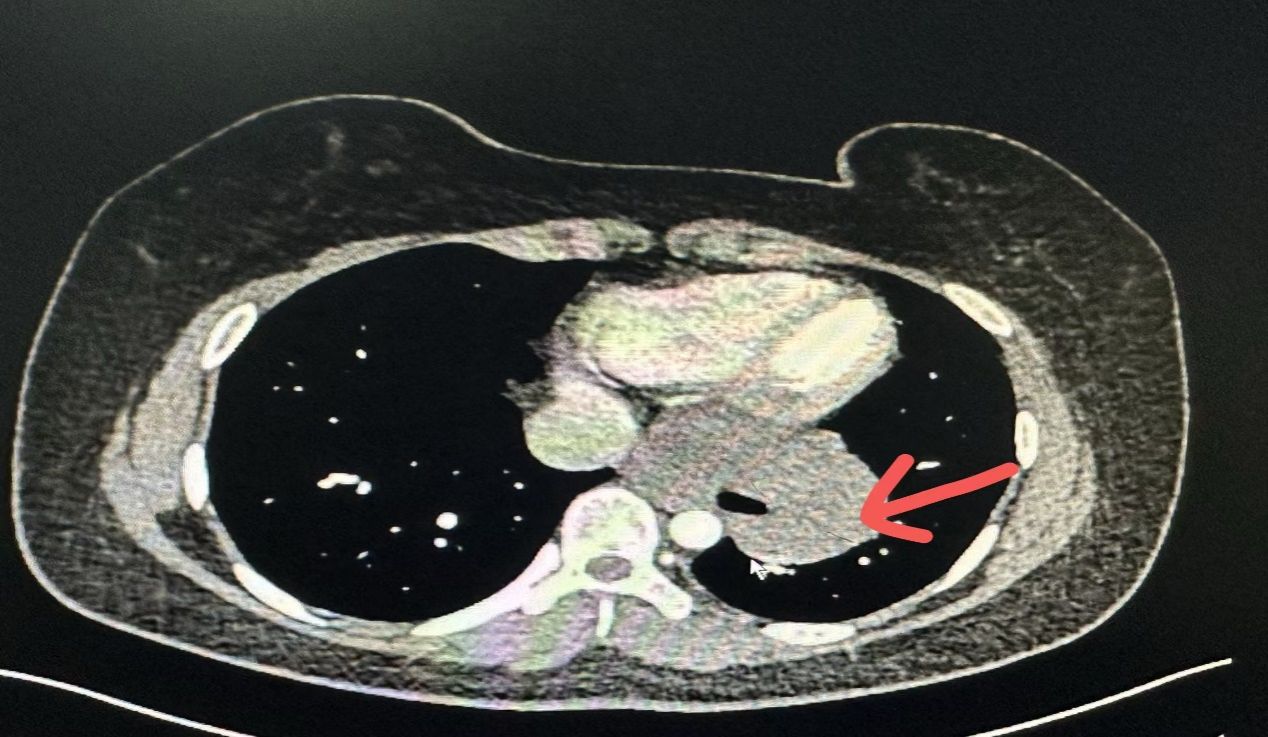

今年19岁刚毕业步入社会的小姑娘小张,平时身体一直很好的她半年前突然出现了进食时吞咽困难的症状,尤其在进食一些硬质食物时哽咽感比较明显,需要喝水送服,起初该症状并未引起小张的重视,也没有去医院检查,但20来天前出现了胸痛的症状,实在不放心的小张去附近医院做了胃镜,胃镜提示食管下段隆起性改变,这可吓坏了小张,为了得到更好的医疗诊治,她来到西安交通大学第二附属医院消化内科,在消化内科做超声内镜提示食管下段至齿状线环3/4周固有肌层一巨大低回声占位,最大截面约5.9x5.4cm,长度约10cm,穿刺活检病理提示:食管平滑肌瘤,面对如此巨大的肿瘤,消化科医生也束手无策,家属知道后也是很紧张,打听得知我院胸外科姜建涛主任是国内胸外科的知名专家,于是慕名找姜主任会诊,姜主任查看过患者资料后当即建议转入胸外科继续治疗。

在转入胸外科后随即为小张完善了术前检查,反复与患者家属沟通交流,告知现阶段最优的解决方法为手术行食管平滑肌瘤剥除术,但因肿瘤巨大,且为环绕食管3/4周生长,术中肿瘤难以剥除或剥除时损伤食管粘膜可能性大,若肿瘤无法剥除或食管粘膜损伤则需行食管部分切除、食管胃弓下吻合术,最终患者家属决定手术治疗。

在2024年10月21日,姜建涛主任医师、李建忠副主任、赵丹文医师为小张实施了手术治疗,术中先尝试胸腔镜手术,腔镜下可见食管下段至贲门巨大隆起性病变,姜主任评估后认为腔镜下操作困难大,遂将操作孔延长至5cm行手术,术中发现肿瘤环食管周生长,完整剥除及其困难,但考虑小张年轻,未避免切除食管而对小张以后的生活造成影响,姜主任团队仔细操作,尽可能为小张保住食管,在姜主任及其团队的精心操作下,手术顺利,手术仅历时一个多小时,便将肿瘤完整剥除,剥除下来的肿瘤长径达到了快13cm,试水检查食管粘膜未损伤。在术后第一天查房的时候小张已经能下地活动了,激动的拉着姜主任的手,感谢姜主任为她成功实施手术并保住了食管,感叹姜主任的高超技艺,现小张一切恢复顺利,已康复出院。